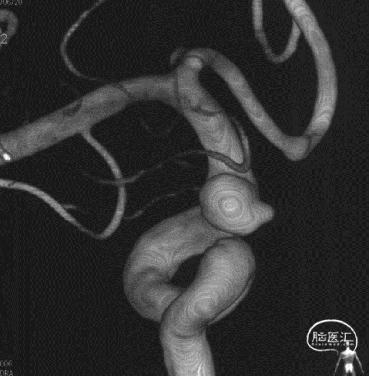

术后半年复查

7、术后半年复查动脉瘤治愈,且未发生支架远近端狭窄及内膜过度增生,治疗效果满意。

8、同侧A1动脉瘤在FD保护下无变化。